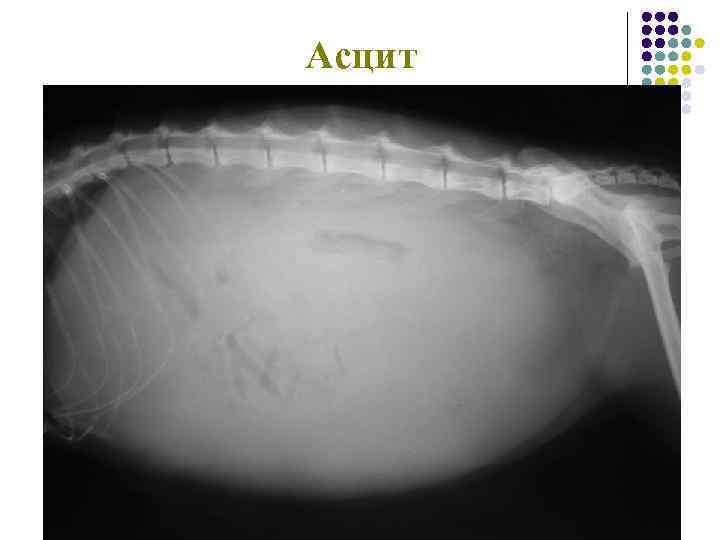

Асцит

Асцит у щенка тойтерьера